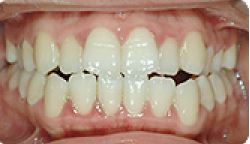

치아성형 전후사례 | 2020.03.06 |